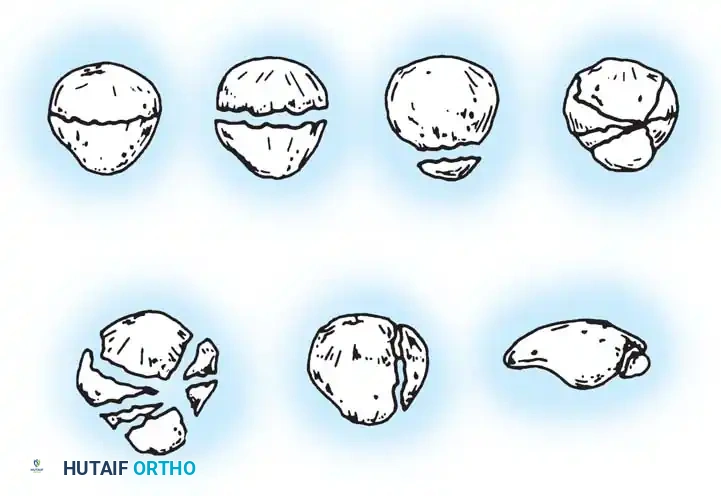

The patella functions as a critical fulcrum, increasing the mechanical advantage of the quadriceps muscle by displacing the extensor mechanism anteriorly from the center of rotation of the knee. A malunited fracture of the patella disrupts this delicate biomechanical balance. The clinical presentation of a patellar malunion is virtually indistinguishable from advanced chondromalacia patellae or severe patellofemoral osteoarthritis.

Disability is directly proportionate to two factors:

1. The degree of step-off or irregularity of the articular surface of the patella.

2. The resultant roughening and eburnation of the contiguous articular surface of the femoral trochlea.

Surgical Indications and Decision Making

In cases of intra-articular malunion with significant step-off (>2 mm) that present late, the articular cartilage is often irreversibly damaged. While intra-articular osteotomy and realignment may be considered in highly selected, very recent malunions in young patients, the procedure of choice for established, symptomatic patellar malunion is typically patellectomy (either partial or total, depending on the extent of the malunion and cartilage loss).